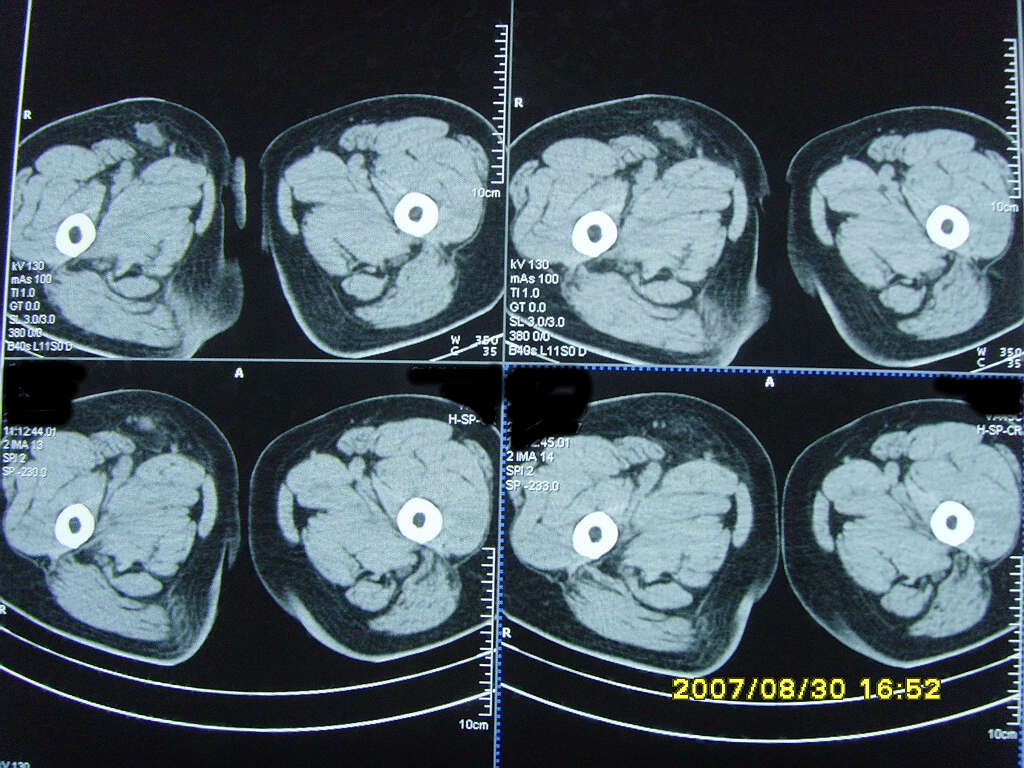

以下是引用zjzjr在2007-9-11 22:21:00的发言:[br]右侧股骨上段前部皮下可见不椭圆形软组织密度影,增强呈环形强化,周围皮下脂肪混浊,考虑感染性病变,不知临床症状如何.